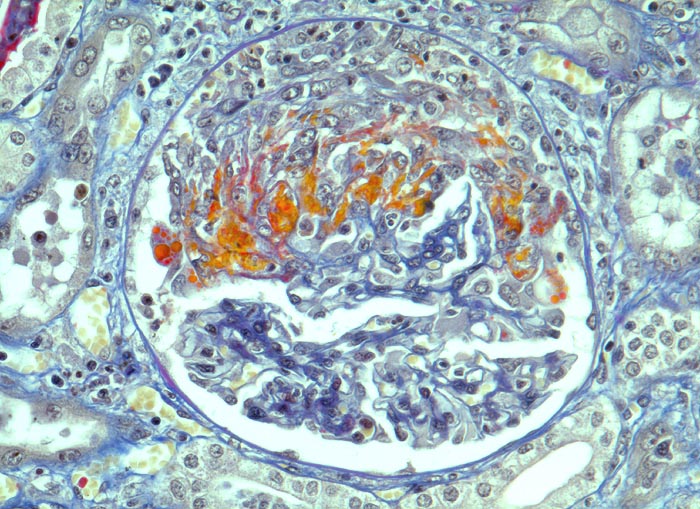

PathoPic – image database / PathoPic ID 5004 - extrakapilläre Glomerulonephritis bei Morbus Wegener

extrakapilläre Glomerulonephritis bei Morbus Wegener

Frische segmentale Schlingennekrosen mit exsudiertem Fibrin und Protein (rot). Beginnende Proliferation von Kapselzellen. Dazwischen einzelne neutrophile Granulozyten.

Halbmondbildung: Sichelförmige Proliferation von Kapselepithelien als Antwort auf eine lokale Fibrinexsudation aus geschädigten/nekrotischen Glomeruluskapillaren.